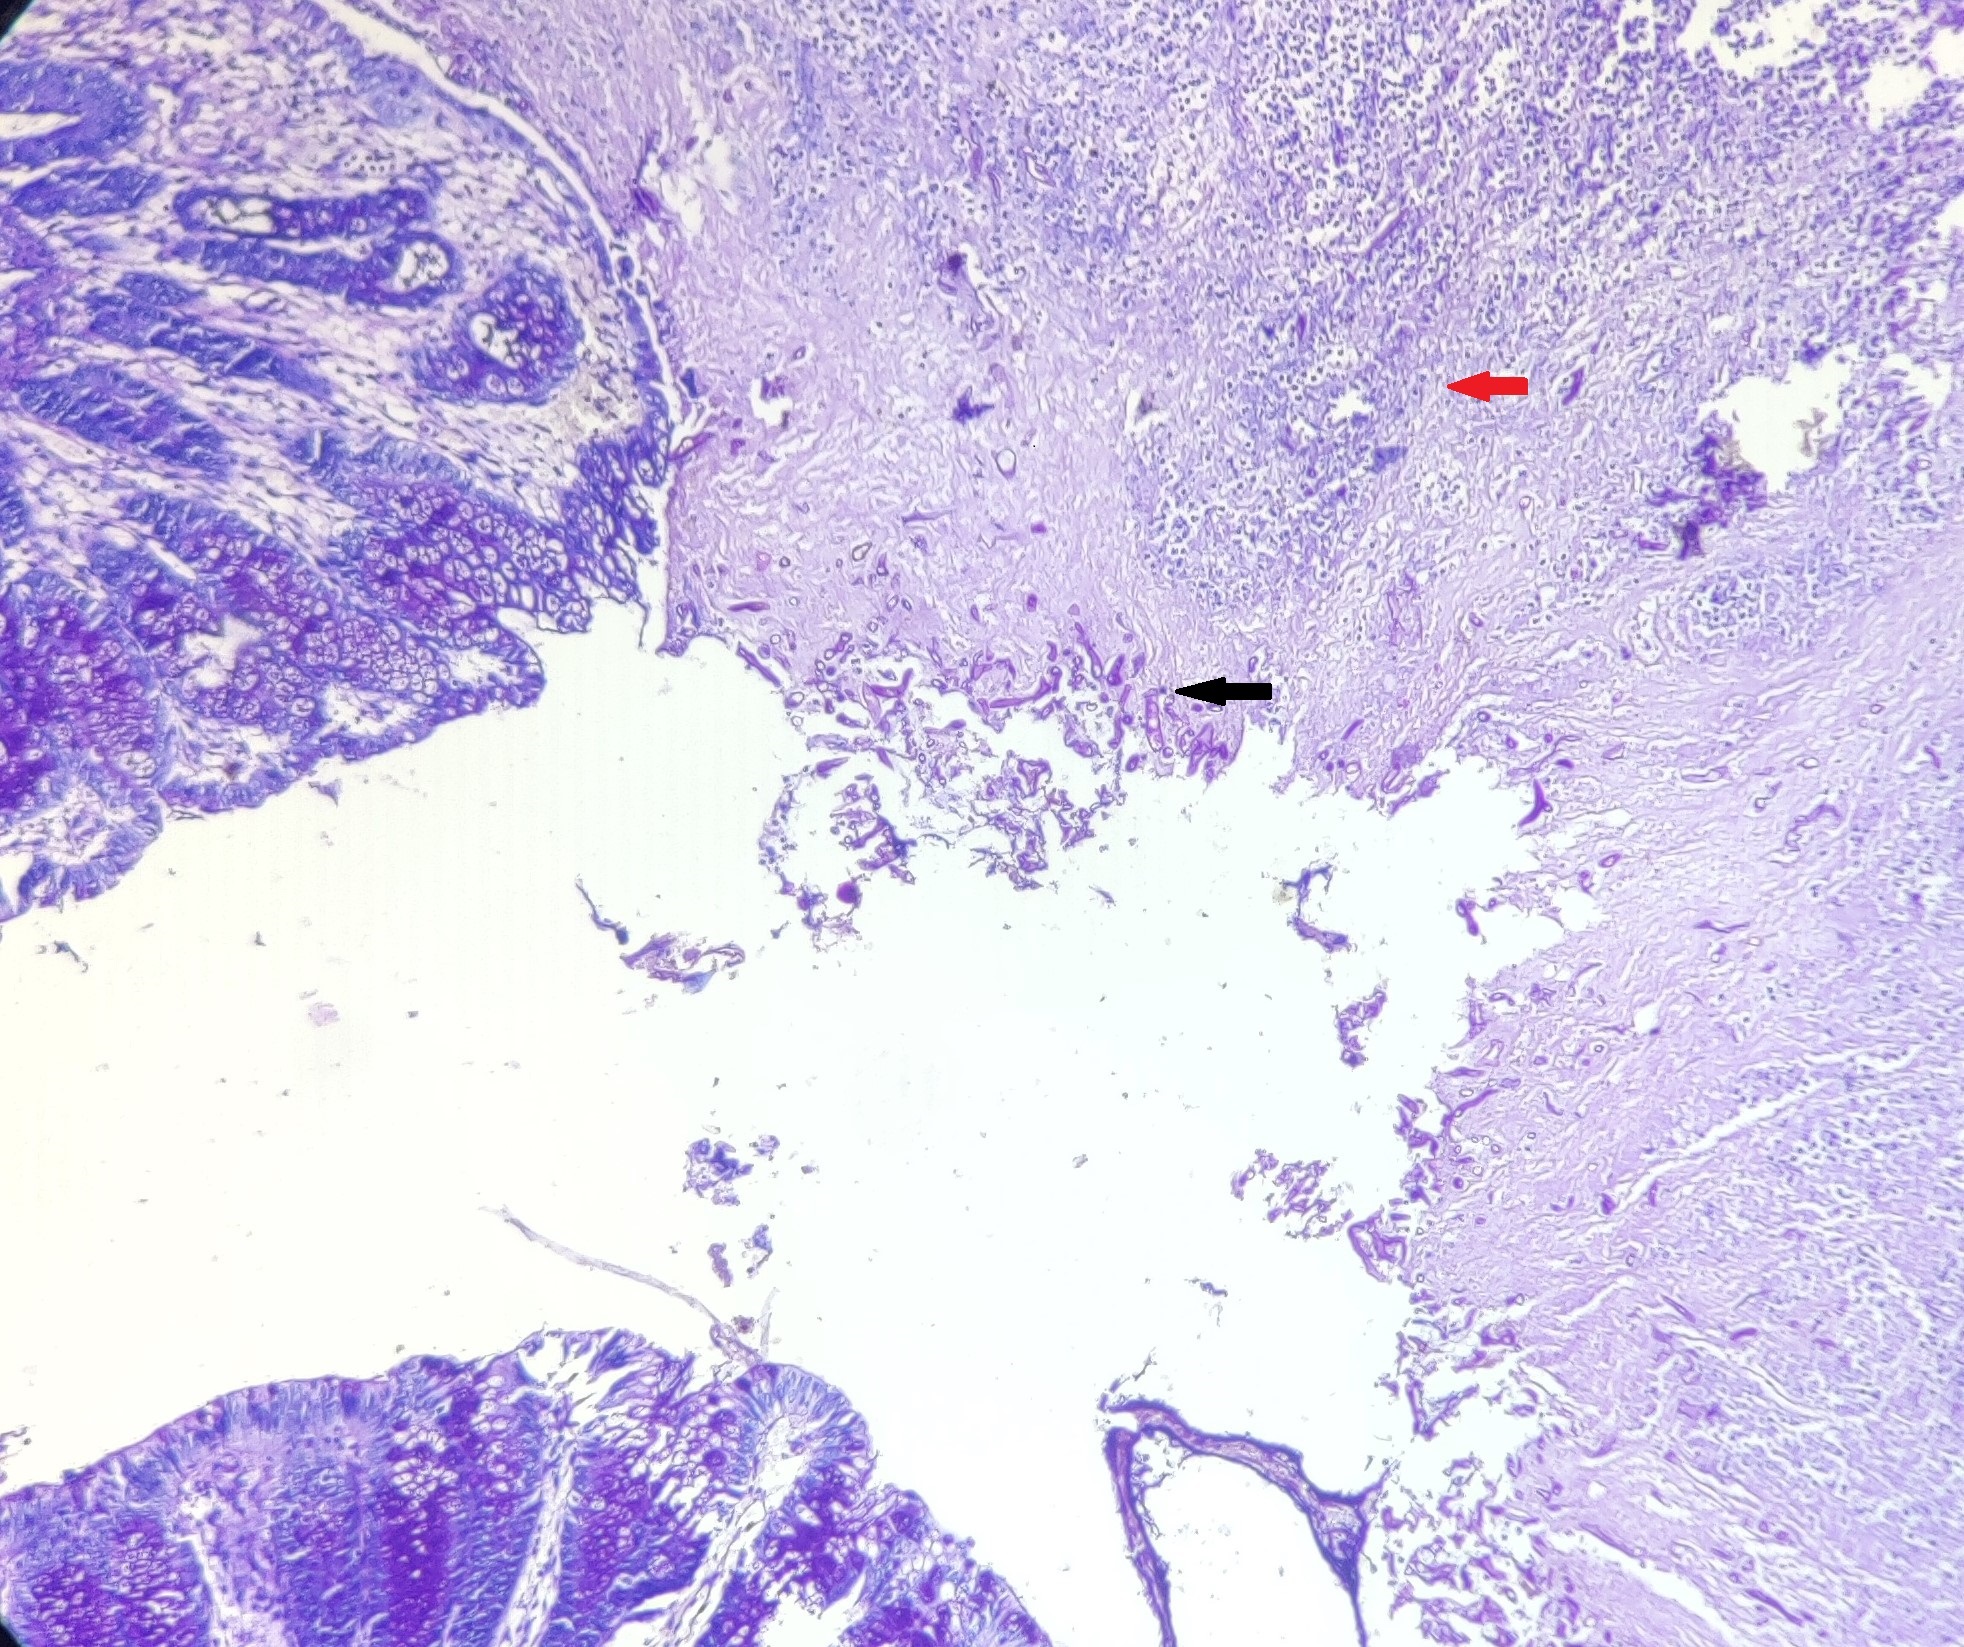

[corresp] Namita Bhutani, Assistant Professor, Department of Pathology, North DMC Medical College and Hindu Rao Hospital, New Delhi, India. E-mail: namitabhutani89@gmail.com

A 10-day-old, male baby born to a primigravida of 23-year at 36 weeks of gestation via emergency Caesarian section for oligohydramnios, was referred to us for abdominal distension and respiratory distress for 3 days. He had not passed stools for 3 days. He was small for gestational age weighing 1.5 kg and had Apgar scores of 4 and 8 at 1 and 5 minutes and had to be put on continuous positive airway pressure (CPAP) soon after delivery. At presentation, the patient’s general condition was poor was on inotropic support for septicemic shock. The nasogastric tube was in situ draining a significant amount of bilious aspirate. On abdominal examination, the abdomen was distended with generalized tenderness and guarding with absent bowel sounds on auscultation. Preliminary lab investigation results were: TLC=40,000 cells/cumm; Platelets=40,000 cells/cumm; CRP=64mg/L. The patient was intubated and taken on hand ventilation and a bolus of intravenous fluid was given along with broad-spectrum antibiotics. X-ray abdomen showed few dilated gut loops with the paucity of air in the intestine. On abdominal ultrasonography, there was minimal inter-gut free fluid with air and fluid-filled dilated gut loops. After hemodynamic stabilization, the patient was taken up for exploratory laparotomy that showed 15ml of sero-feco-purulent peritoneal fluid and a 5 cm gangrenous and perforated segment of the proximal sigmoid colon with thick meconium/fecal matter in the left iliac fossa. A segment of the proximal ileum was found stuck to the involved sigmoid colon segment leading to kinking and perforation at its apex. Therefore, resection of involved gangrenous sigmoid colon and perforation bearing segment of proximal ileum was done with end-to-end colo-colic and ileo-ileal anastomoses. The histopathological examination showed sigmoid colon had the aggregate of Langhans and foreign body giant cells with areas of necrotic exudates and serositis and the detection of many wide, ribbon-like, sparsely septate fungal hyphae with wide angle branching (approximately 90 degrees) characteristic of mucormycosis without any angioinvasion (Fig. 1). The postoperative period was uneventful and the patient was discharged on the seventh postoperative day after he had started accepting orally and passing flatus and stools normally. He is on regular follow-up, thriving well with a weight appropriate for his age.

Figure 1

Micro-sections from gut revealing dense inflammatory infiltrate (yellow arrow), numerous multinucleated giant cells (red arrow), and fungal hyphae (black arrow).